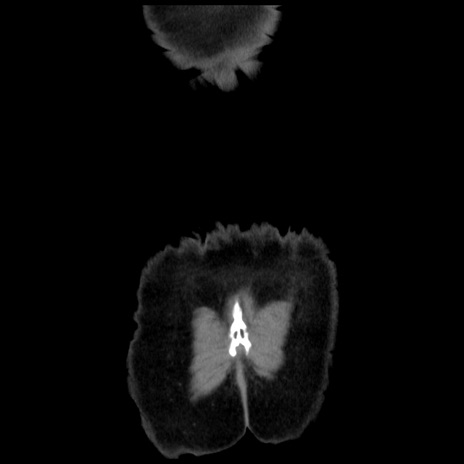

横断像